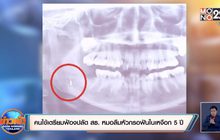

คนไข้เตรียมฟ้องปลัด สธ. หมอลืมหัวกรอฟันในเหงือก 5ปี